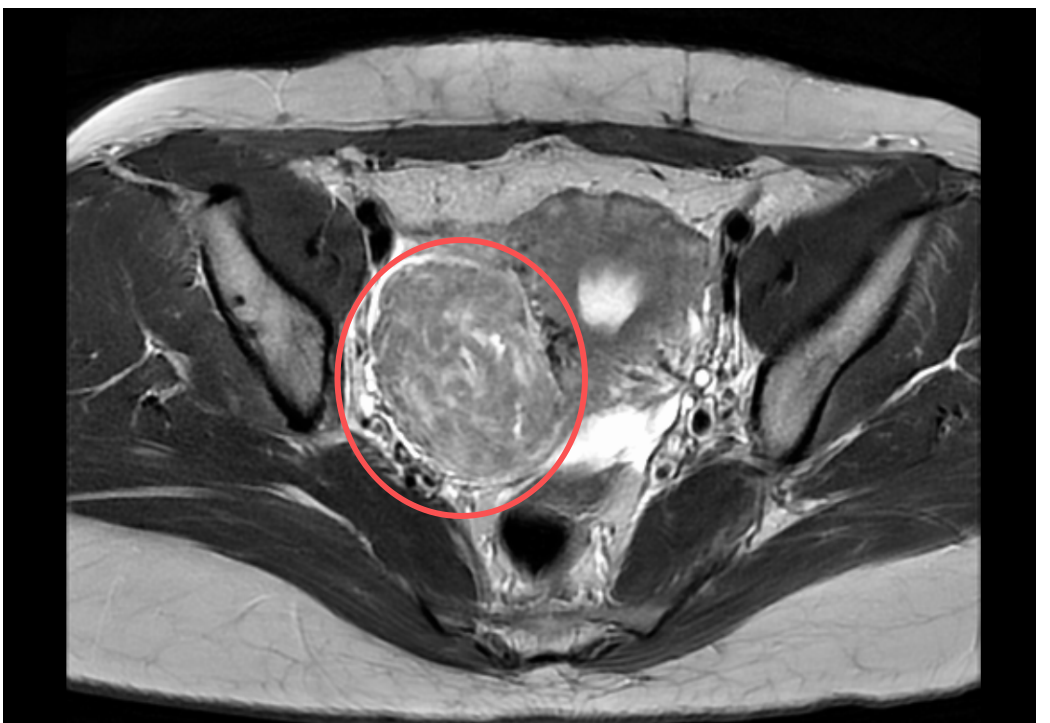

近1年来,吴女士的经期出现变化,月经量也比既往多了一倍,加上腰痛、尿频症状逐渐出现并加重,来到广州医科大学附属第三医院妇科门诊检查后发现,子宫肌瘤远不止一个,最大的一个堪比拳头,而且向阔韧带凸出,长在了子宫阔韧带上。

“阔韧带是维持子宫位置的重要韧带之一,此外,供应子宫的重要血管都走形其中,两叶间有丰富的疏松结缔组织,且输尿管也与其毗邻。”广州医科大学附属第三医院妇科主任、主任医师刘娟解释,阔韧带肌瘤是子宫肌瘤的一种特殊类型,由于阔韧带血供丰富,子宫肌瘤在此生长易“无拘无束”,一旦压迫输尿管,还会导致泌尿系统症状,长此以往甚至影响肾功能。”

作为一种特殊类型的子宫肌瘤,子宫阔韧带肌瘤手术难度较高,除了术中易出现大出血,还需要精细解剖,避免损伤临近的重要组织和器官。

手术当日,刘娟全程精细化操作并严控出血风险,成功提出了巨大阔韧带肌瘤,术中出血仅20mL,且并未对膀胱、输尿管等周围脏器造成损伤。

文中提到的阔韧带肌瘤就是典型的案例,“这一子宫肌瘤长在了险要的位置,向前长会压迫到膀胱,出现尿频、尿急、排尿困难等情况,向下长会压迫输尿管,影响到肾脏的健康,如果压迫到盆腔的血管,可能下肢会水肿或静脉曲张。”这就是特殊类型的子宫肌瘤对健康可能造成的危害。